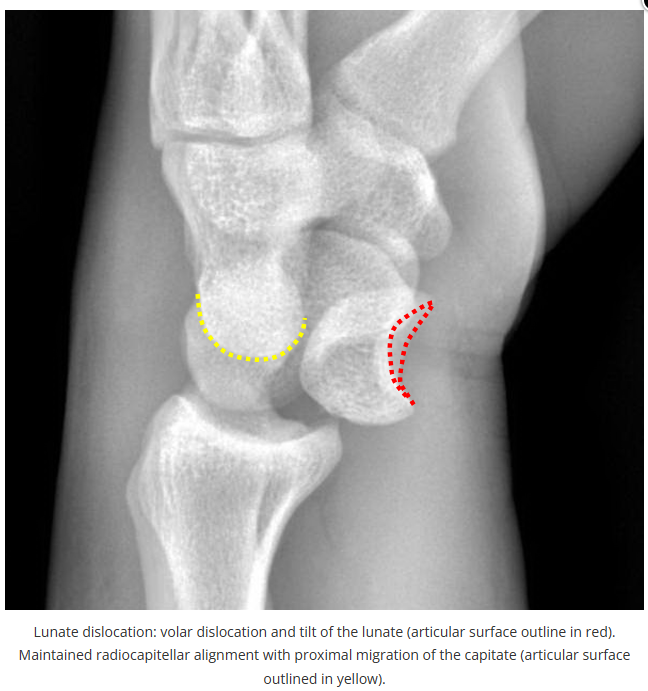

X线读片是骨科医生的基本功。

今天是腕部与手的X线片。所有X线片都

带有标注和说明

,可以选择长按图片,

自动翻译相关说明

进阶篇